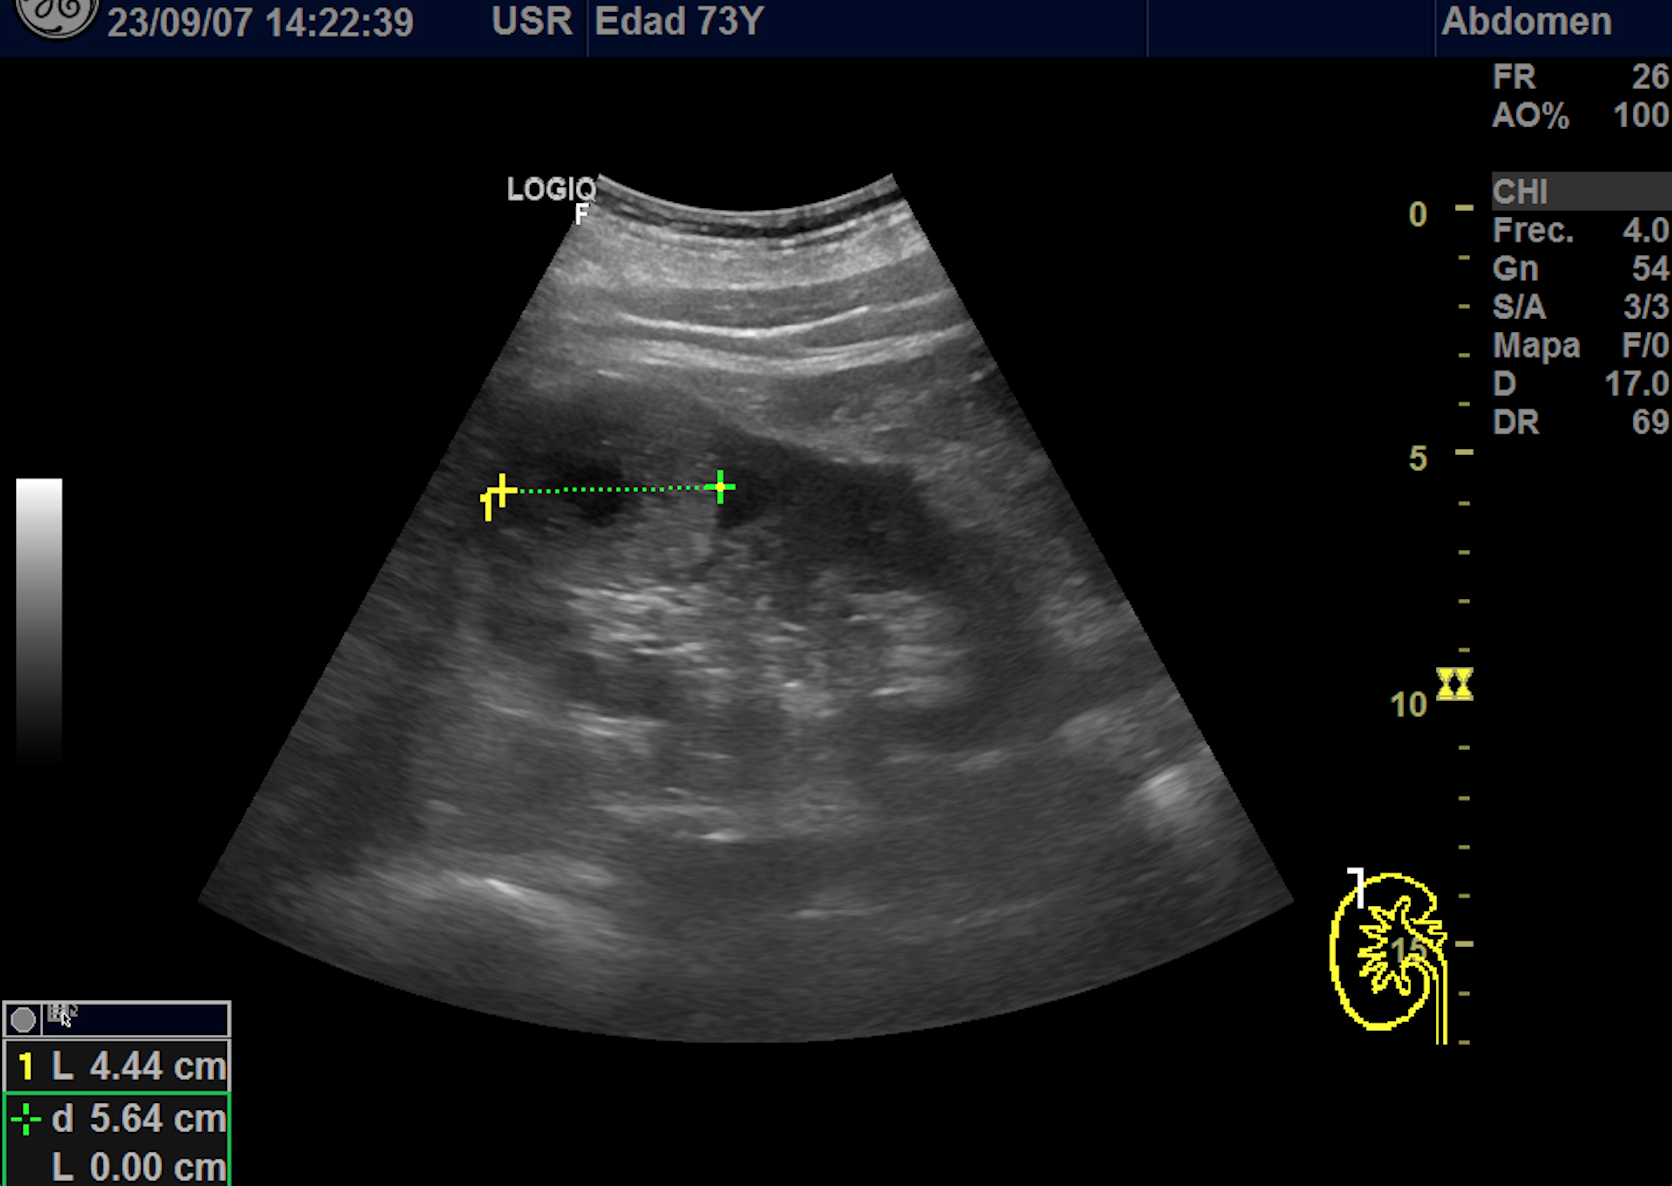

Hallazgos ecográficos

En polo superior de riñón derecho se observa una imagen redondeada, bien delimitada, isoecoica con un área central hipoecoica con vascularización periférica y central de 4,1 x 4,18 x 4,94 cm.

Se le realiza un TAC abdomino-pélvico donde se observa a nivel de valva posterior del meso riñón derecho se observa una masa sólida de 5,1 x 4,9 x 5 cm compatible con proceso neoformativo, la lesión es exofítica de contornos bien definidos, tras contraste IV muestra un realce hipervascular con área central hipocaptante probablemente en relación con necrosis. Resto de estudio de extensión negativo.